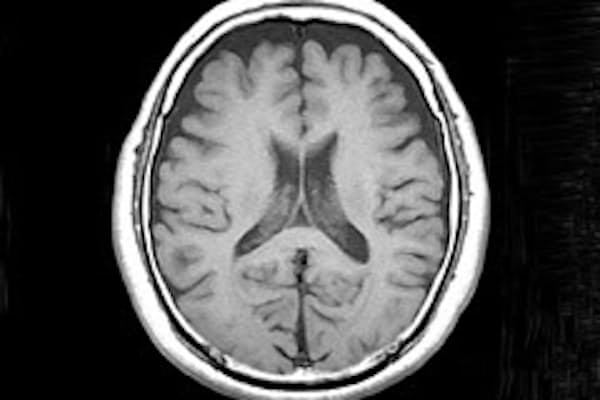

たまたま見つけた脳萎縮の進行から 色々なことを想像する 鹿児島認知症ブログ

脳萎縮が招く認知症 その症状と予防法を医師に聞いた マイナビニュース